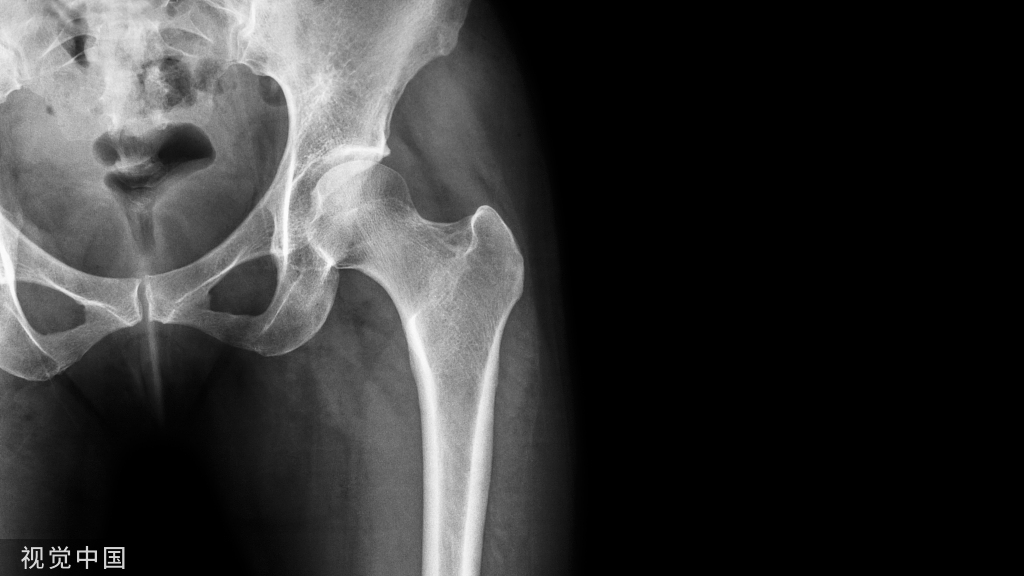

5、X线检查:能证实脱位的类型,还能发现是否合并骨折。